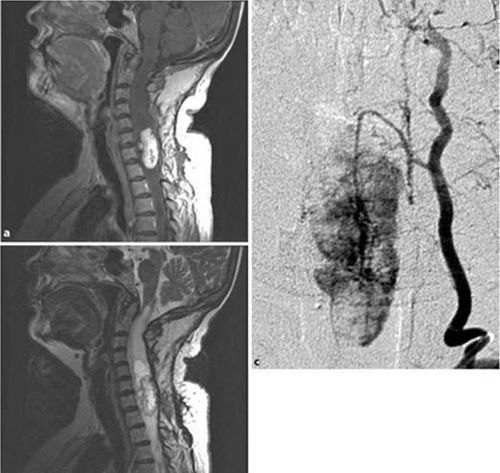

- Trên MRI, các u màng ống nội tủy thường nằm ở phía trung tâm tủy sống. Chúng thường tăng ngấm thuốc, thể hiện hình thái tăng ngấm thuốc lan tỏa sau khi tiêm gadolinium, liên quan đến chảy máu, và thường có rỗng tủy. Các u màng ống nội tủy là đồng tín hiệu hoặc giảm tín hiệu trên T1 và tăng tín hiệu trên T2. Một phần ba các u màng ống nội tủy có một viền giảm tín hiệu mạnh thấy ở các cực của khối u do tích tụ hemosiderin, được gọi là dấu hiệu đội mũ (cap sign). Nó có thể do chảy máu, là thường gặp trong u màng ống nội tủy so với u tế bào hình sao. Các u tế bào hình sao của tủy sống thường nằm lệch tâm, có ranh giới mờ nhạt, và đồng tín hiệu hoặc giảm tín hiệu tương đối so với tủy sống trên T1 và tăng tín hiệu trên T2. Các nang trong khối u và rỗng tủy có thể có nhưng ít gặp hơn so với các u màng ống nội tủy. Dấu hiệu đội mũ thường không có trong u tế bào hình sao của tủy sống. U nguyên bào đệm tủy sống biểu hiện là một khối nội tủy lan rộng, thâm nhiễm với tín hiệu cao trên T2 và tăng ngấm thuốc không đồng nhất trên T1 sau tiêm thuốc.

Sự khác nhau trên điện quang giữa u màng ống nội tủy và u tế bào hình sao là có giá trị để lập kế hoạch điều trị trước phẫu thuật. Cắt toàn bộ đối với các khối u tế bào hình sao là khó vì bản chất thâm nhiễm của nó. Trái lại, các khối u màng ống nội tủy kinh điển được biết rằng có ranh giới rõ với mô tủy sống bình thường lân cận và do vậy dễ cắt hoàn toàn khối u hơn.

4.3 U nguyên bào mạch máu tủy sống

U nguyên bào mạch máu là u phát triển chậm và lành tính, bao gồm các tế bào gốc trung mô tân sản và mạng lưới mao mạch nhỏ rất phong phú. Chúng thường gặp ở tiểu não và thân não.

U nguyên bào mạch máu tủy sống biểu hiện với các triệu chứng đau, giảm cảm giác và cơ tròn không tự chủ. Thiếu sót vận động xuất hiện muộn vì loại u này thường ở tủy sống sau.

Các dấu hiệu MRI của u nguyên bào mạch máu tủy sống là một khối tăng ngấm thuốc với tạo nang và tạo đường hầm. Các ổ trống dòng chảy có thể thấy dưới dạng nốt vì có các mạch máu nuôi. Khi tổn thương lớn hoặc ở hành não, chụp mạch số hóa xóa nền có thể cần thiết để nhìn rõ các động mạch nuôi như một phần trong việc lập kế hoạch trước phẫu thuật. Các kết quả lâm sàng là rất tốt nếu u nguyên bào mạch máu tủy sống được cắt bỏ hoàn toàn.